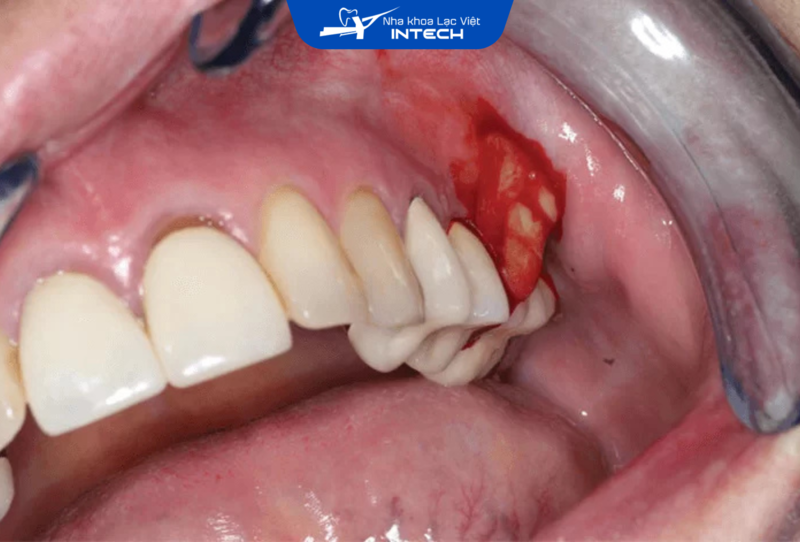

Nhiễm trùng vùng quanh Implant có thể xảy ra ngay sau khi thực hiện cấy ghép, đặc biệt trong giai đoạn vết thương đang lành. Đây là một trong những nguyên nhân phổ biến dẫn đến tình trạng chảy mủ quanh răng Implant.

Nguyên nhân chủ yếu gây nhiễm trùng là do quy trình phẫu thuật không đảm bảo vô trùng tuyệt đối, tạo điều kiện cho vi khuẩn xâm nhập vào vùng cấy ghép. Vi khuẩn phát triển sẽ gây ra tình trạng viêm nhiễm, phá hủy mô mềm và dẫn đến xuất hiện dịch mủ ở vùng cắm Implant.

Nhiễm trùng vùng quanh Implant là một trong những nguyên nhân phổ biến dẫn đến tình trạng chảy mủ quanh răng Implant